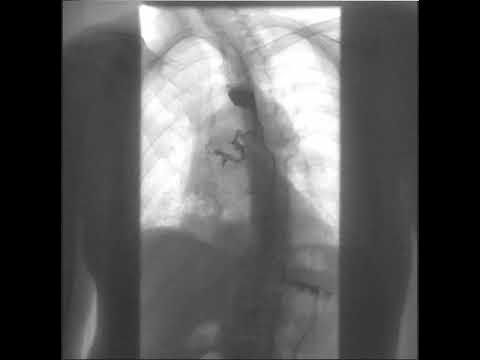

A 50-year-old man presented to the emergency department with a 5-day history of shortness of breath, chest pain, and a cough. Fifteen days before presentation, he had received a diagnosis of large-cell neuroendocrine carcinoma of the lung with brain metastases. The oxygen saturation was 93% while the patient was breathing ambient air. The physical examination was notable for diminished breath sounds in the right lower lobe, as well as paroxysms of cough after fluid intake. Computed tomography of the chest showed diffuse bilateral interstitial infiltrates, as well as the known lung lesion surrounding the middle third of the esophagus. Testing for severe acute respiratory syndrome coronavirus 2 (SARS-CoV-2) was negative. Water-soluble contrast esophagography revealed material passing from the esophagus to the right bronchial tree and ascending to the right main bronchus and trachea as the patient coughed (see video). A diagnosis of bronchoesophageal fistula due to lung carcinoma was made. A covered, self-expanding metal stent was placed in the esophagus, which alleviated the patient’s cough and chest pain. Treatment with chemotherapy was initiated; however, the patient transitioned to hospice care and died 4 weeks after presentation.